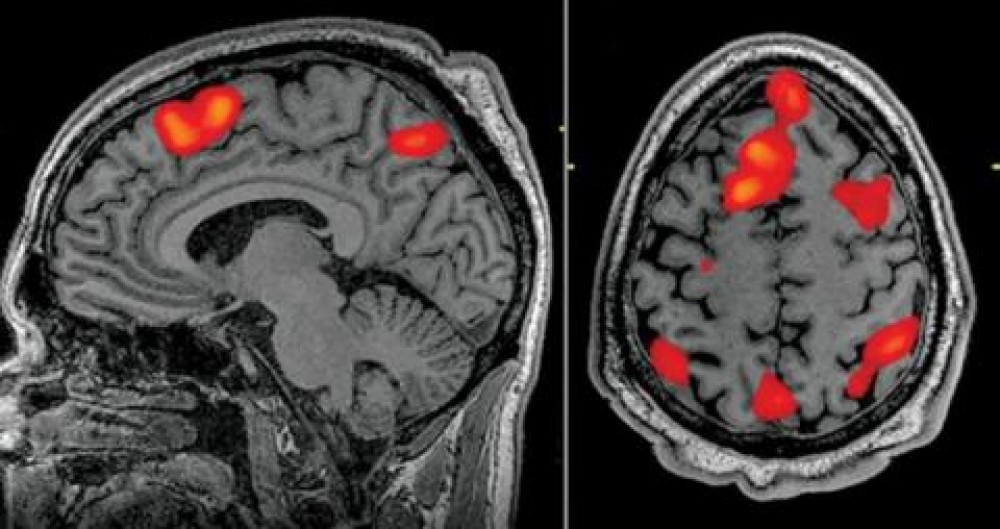

وباستخدام التصوير بالرنين المغناطيسي الوظيفي (fMRI)، أنشأ فريق من جامعة تكساس في أوستن واجهة بين الدماغ والحاسوب قادرة على إنشاء جمل كاملة بناء على ما يفكر فيه الناس.

ويتم قياس نشاط الدماغ باستخدام ماسح الرنين المغناطيسي الوظيفي بعد تدريب مكثف لوحدة فك التشفير، حيث يستمع الفرد إلى ساعات من البث الصوتي في الماسح الضوئي. ولاحقا، طبعا بشرط أن يكون المشارك منفتحا على فك تشفير أفكاره، فإن استماعه لقصة جديدة أو تخيله لرواية قصة يسمح للتقنية الجديدة بتوليد نص مطابق لنشاط الدماغ وحده.